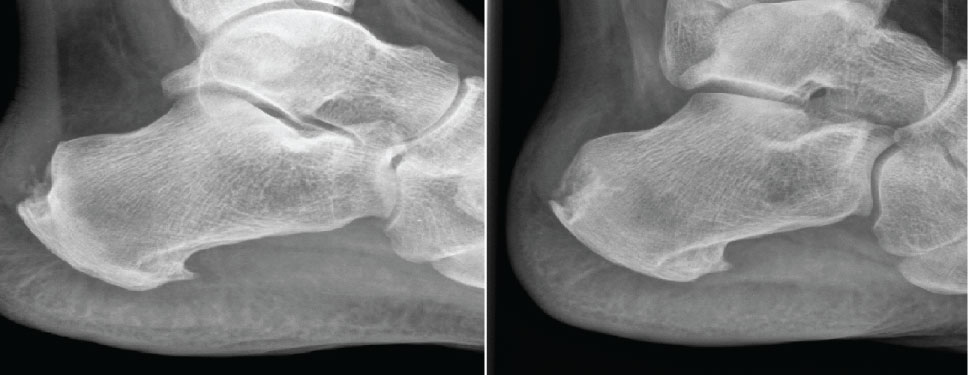

With regard to the change in millimeters (mm) of the calcification, all of the patients showed a decrease in the size of calcification. The radiological change in Achilles CT was significant; decreased from 10 ± 5.3 to 5.3 ± 5.22 mm (p = 0.0186), (Table 2, Figures 2, Figure 3, Figure 4, Figure 5 and Figure 6).

Figure 2: Case 1: In a 50-year-old female, after 10 sessions of treatment, pain decreased from 8/10 to 1/10 and size of calcification decreased from 12 to 6 mm. View Figure 2

Figure 3: Case 2: In a 38-year-old female, after 20 sessions of treatment, pain decreased from 10/10 to 2/10 and size of calcification decreased from 3 to 2 mm. View Figure 3

Figure 4: Case 3: In a 47-year-old male, after 20 sessions of treatment, pain decreased from 7/10 to 4/10 and size of calcification decreased from 10 to 0 mm. View Figure 4

Figure 5: Case 4: In a 57-year-old female, after 15 sessions of treatment, pain decreased from 9/10 to 4/10 and size of calcification decreased from 9 to 4 mm, evaluated by sonography. View Figure 5

Figure 6: Case 5: In a 57-year-old female, after 15 sessions of treatment, pain decreased from 5/10 to 0/10 and size of calcification decreased from 6 to 0 mm, evaluated by sonography. View Figure 6